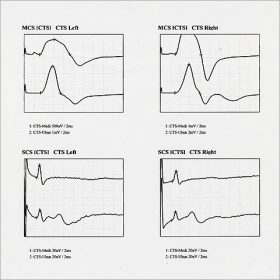

神経伝導検査

しびれ、痛み、麻痺などの神経症状の程度を数値やグラフで客観的に評価します。

得られたデータを実際の症状と比較し、診断の補助や確認を行います。

20~30分ほどで行う検査です。その場で結果の説明をさせて頂きます。

電気刺激を加え、目的とする筋・神経が反応するまでの時間や反応の持続時間、波の高さや波形、左右差などを評価し病変の部位や拡がりを測定します。